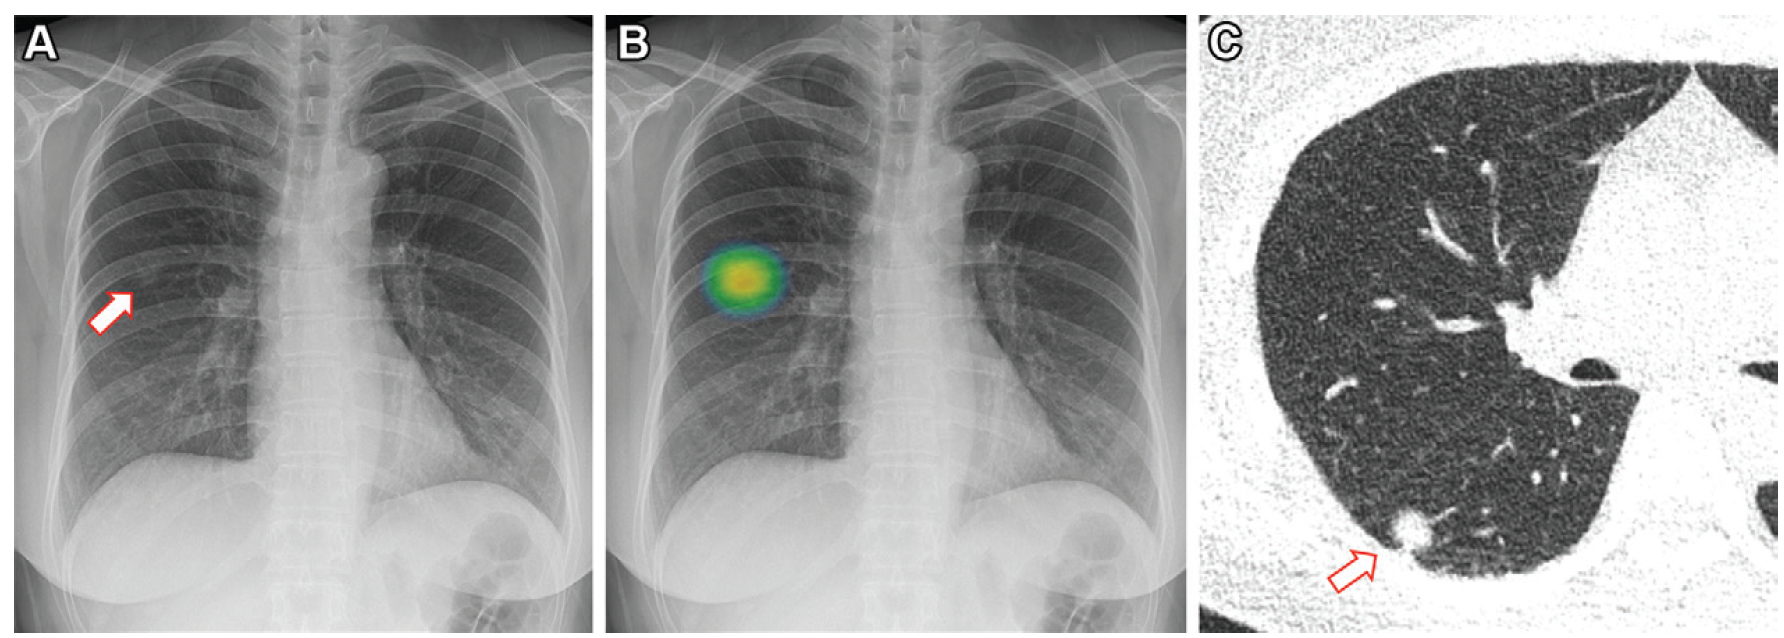

In an external validation data set for a deep learning bone-suppressed (DLBS) model, researchers found that adjunctive use of the DLBS model led to a nearly 15 percent increase in sensitivity for detecting pulmonary nodules on chest X-rays in comparison to radiologist assessment.